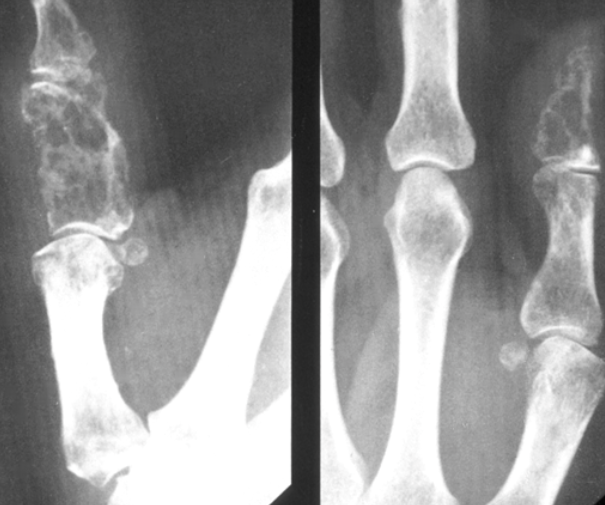

Xrays